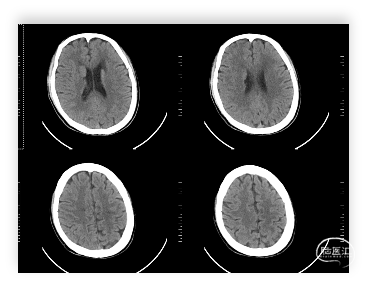

头颅MRI:左侧额顶叶急性脑梗塞;桥脑左份、双侧基底节、右侧脑室旁及双侧额叶多发腔隙性脑梗塞;双侧脑室旁及额顶叶轻度白质脱髓鞘;双侧上颌窦、筛窦、蝶窦炎;脑MRA示①右侧椎动脉纤细(变异)②左侧大脑后动脉P2段局部狭窄③左侧颈内动脉眼段局部严重狭窄④脑动脉轻度硬化改变,请结合临床及其他检查协诊。

缺血性脑血管病

诊断依据:1、老年男性,静态起病。2、查体右侧肢体肌力5级差,右侧病理反射阳性。3、头颅MRI示:左侧额顶叶急性脑梗塞。